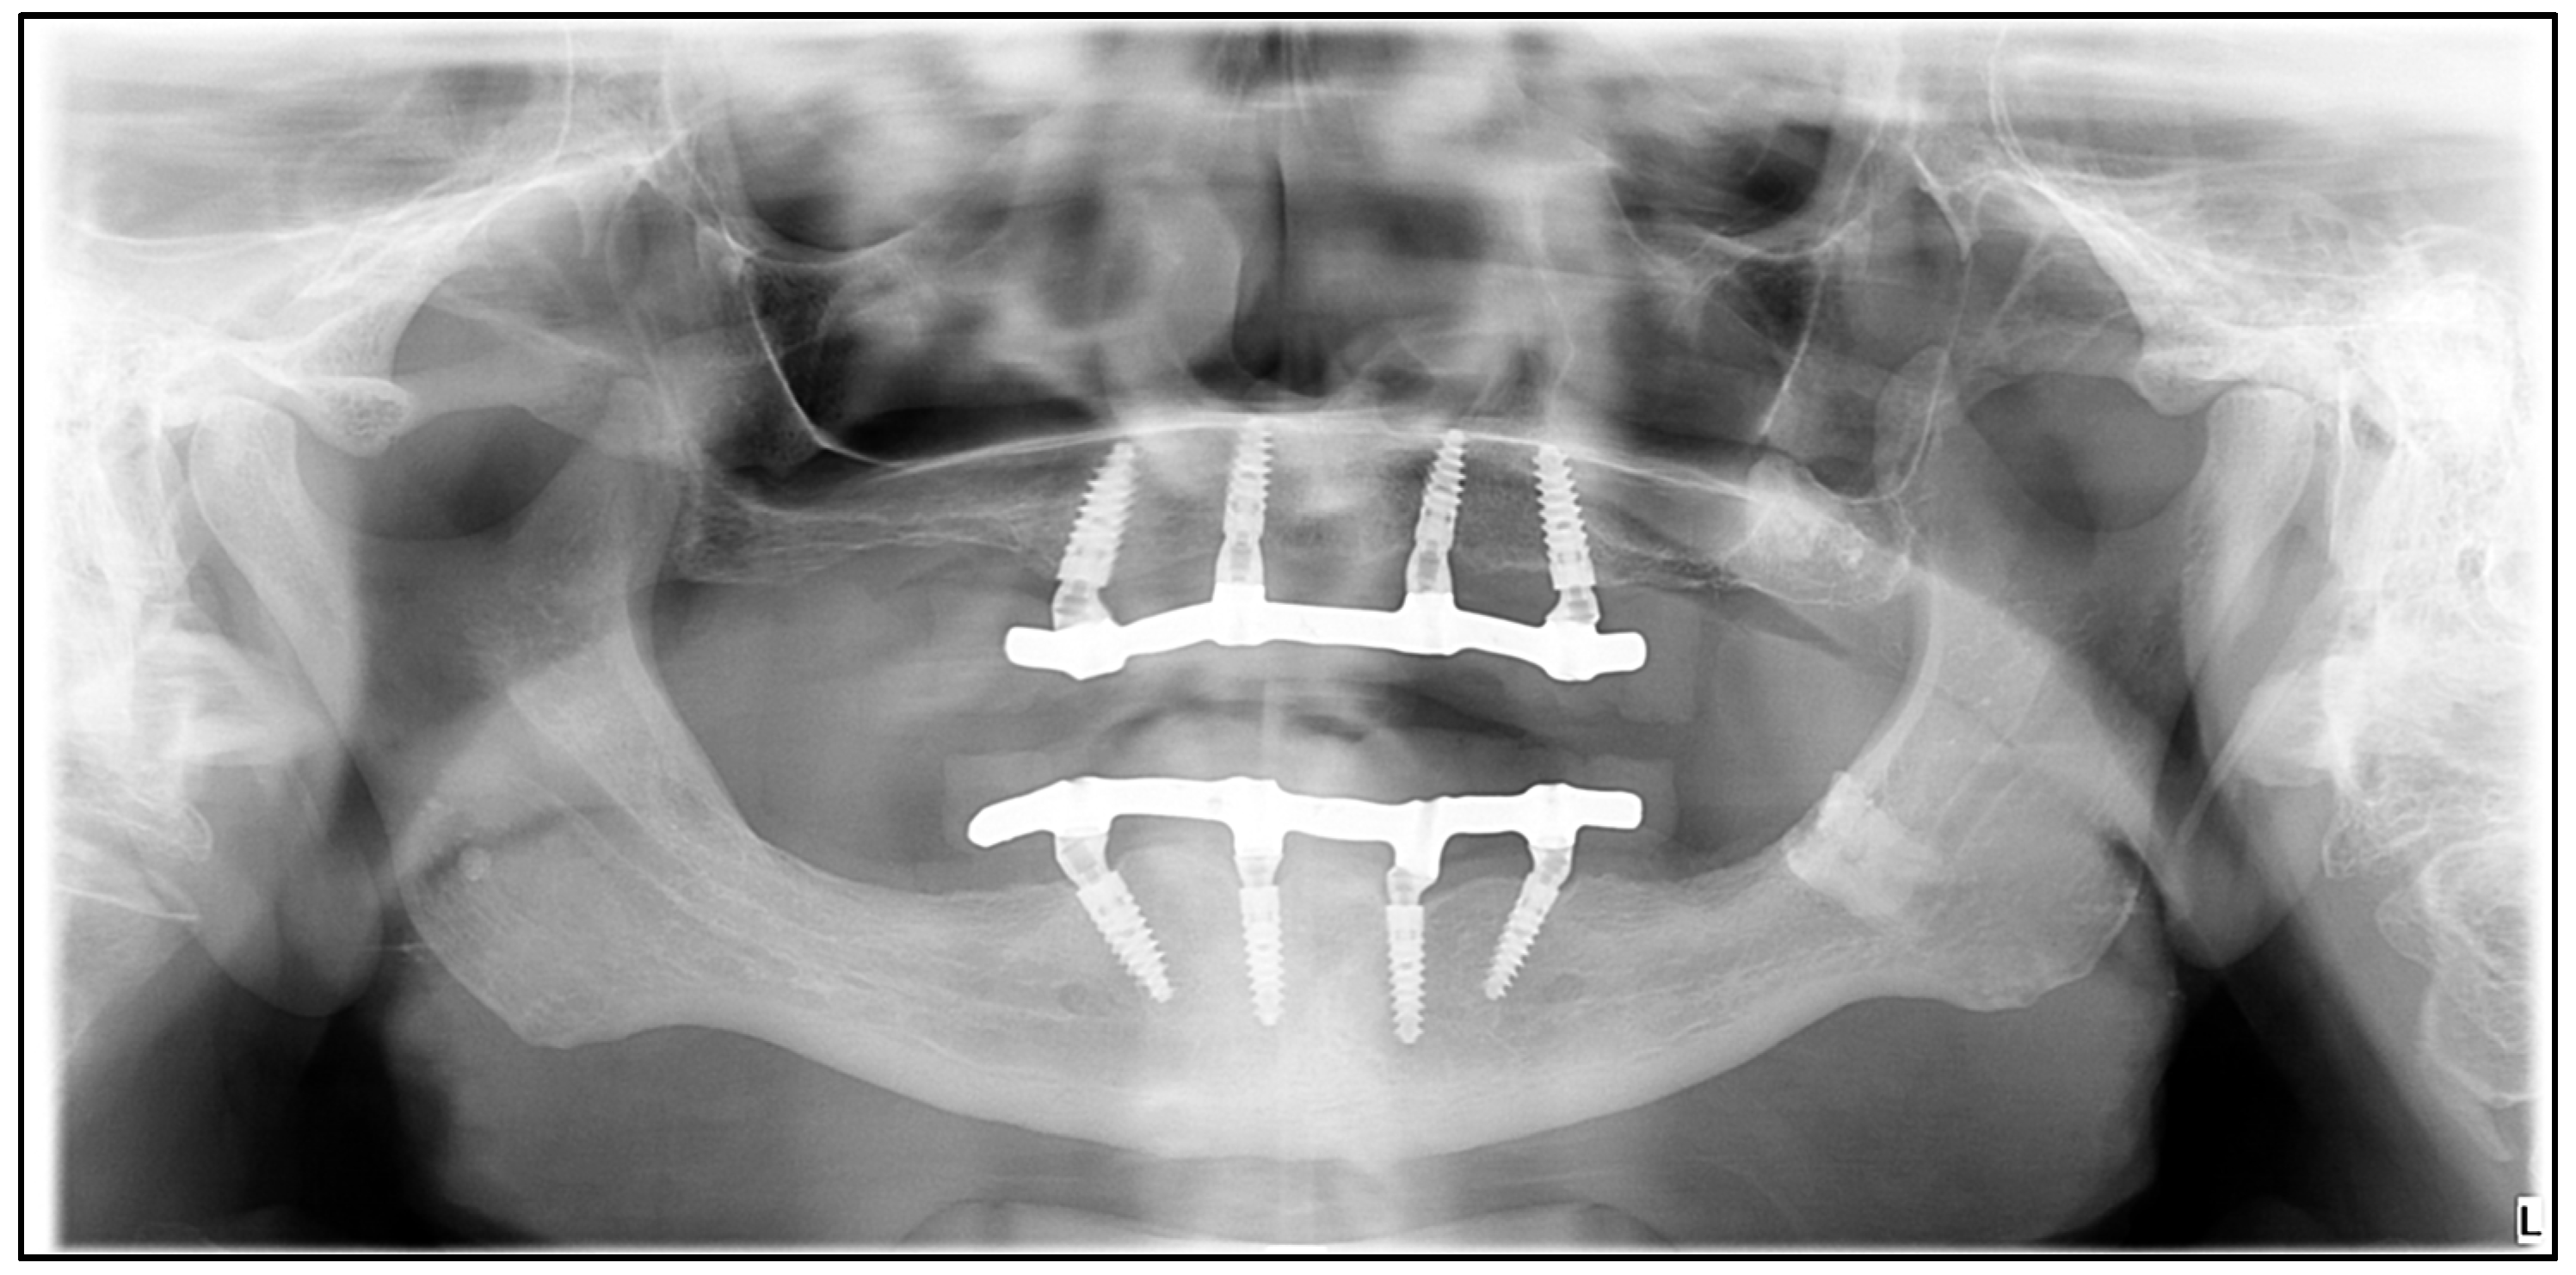

2.3. Modeling